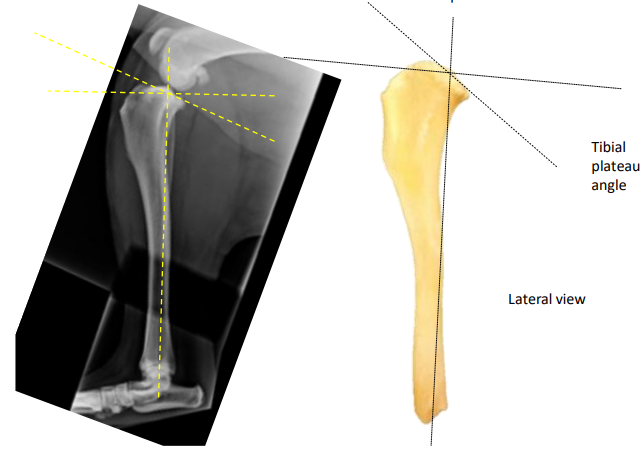

<p>What do these images show?</p>

What do these images show?

proximal tibial articular surface has backward slope